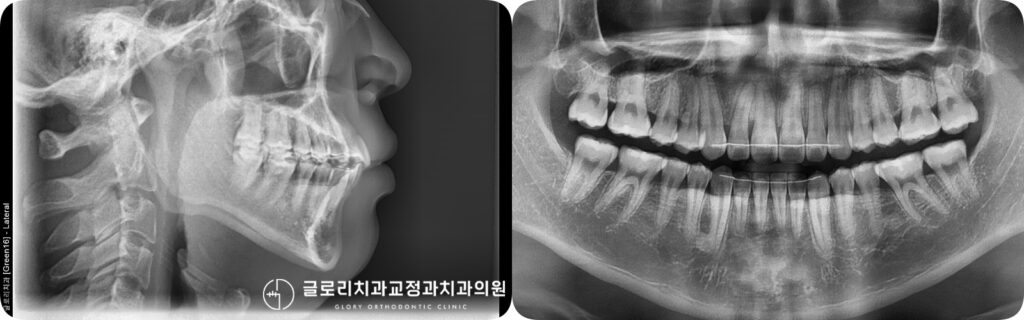

이제 큰 틀의 배열이 완성된만큼 정밀한 교합과 치열을 완성하기 위한 마무리

단계로 넘어가게 되는데요,필요에 따라 치간삭제를 통해 인접치 사이의 접촉면을

미세하게 다듬어 사이 간격을 균일하게 조정할 수 있습니다.

치간삭제는 법랑질의 극히 일부를 삭제하는 처치로 자연치 건강에 영향을 주지 않는

범위 내에서 이루어지며 보다 자연스러운 형태와 긴밀한 교합 접촉을 만드는 데 도움이 됩니다.

종결

이후 교정이 마무리 된 구강의 모습입니다. 초진시 겹치고 틀어져있던 전치부 총생이

개선되어 이가 가지런하게 배열되었으며 좌측으로 편위되어있던 정중선도 일치합니다.

이번 상봉동 교정치과 에서 준비한 케이스의 경우 비발치 교정을 통해 자연치를 보존하면서

심미성을 향상시키게 되었는데요. 이처럼 교정은 치아를 가지런히 만드는 것을 넘어

올바른 교합과 구강 건강의 장기적인 유지를 목표로 합니다.

치료기간 : 24.01.10~26.03.13